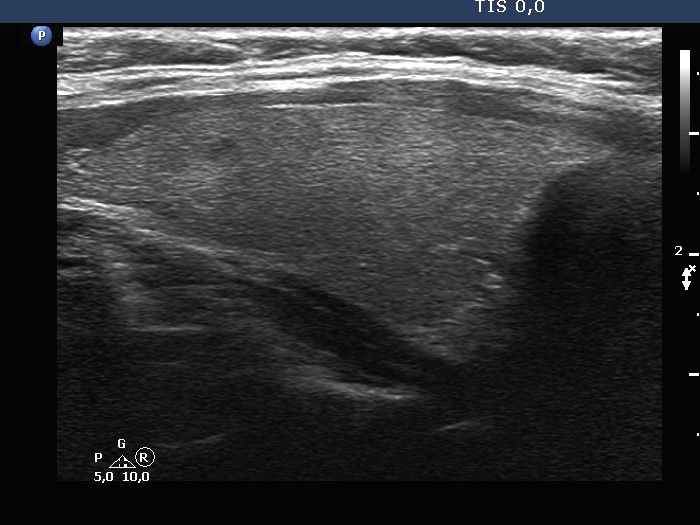

The composition of the nodule - case 2103 (ultrasonographic picture 5)

Left lobe, longitudinal scan.